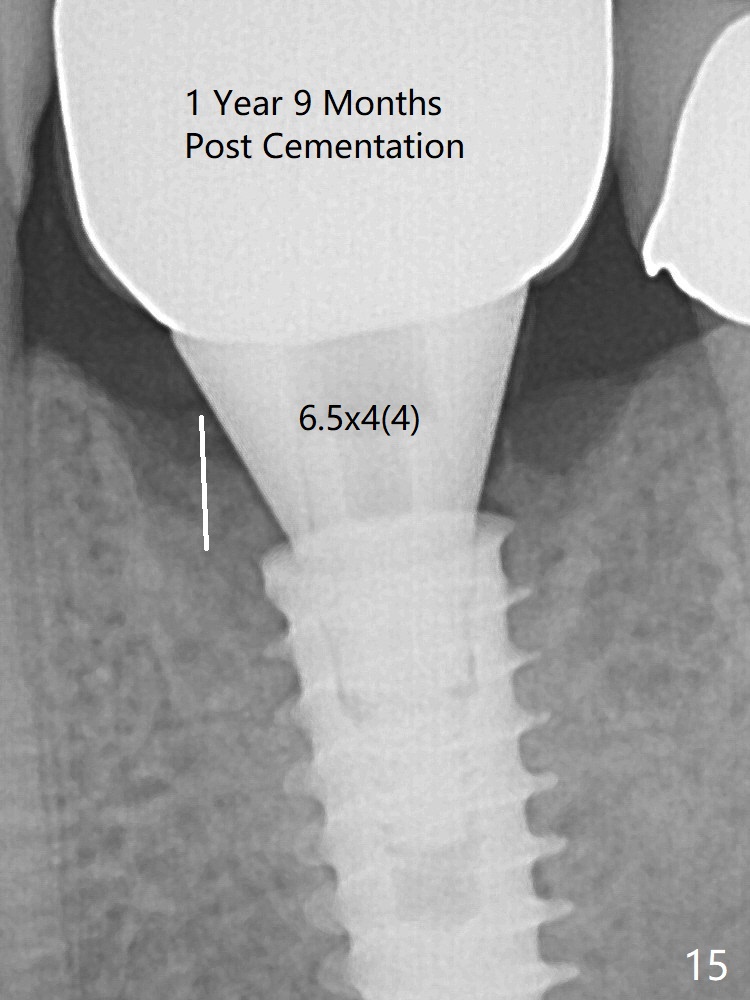

New bone has apparently covered the implant plateau 8 months postop (3 months post cementation (Fig.13 arrows)). The lower two-thirds of socket have disappeared. Bone density between threads increases 9 months post cementation (Fig.14). There is 2 mm bone superior to the implant plateau mesial and distal 1 year 9 months post cementation (Fig.15,16).